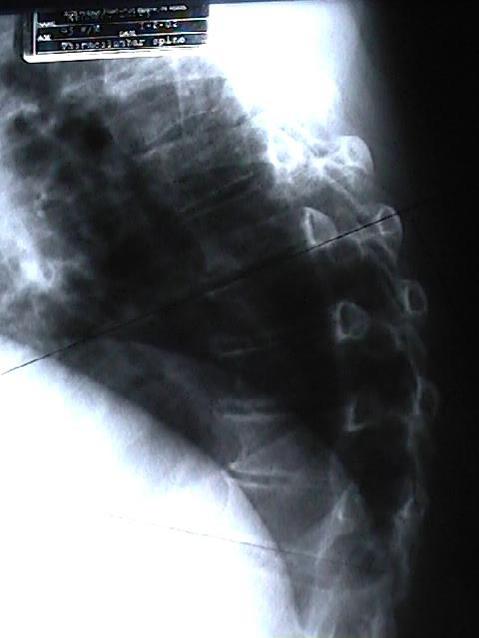

Now, medical literature points out that AS patients have a 5-fold higher risk of clinical spine fracture and a 35% increased risk of non-vertebral fracture. This extra risk peaks early, in the first 2 and a half years of AS disease. It is recommended that AS patients be assessed for fracture risk early after their AS diagnosis. (3) Trust Poulin Chiropractic of Herndon and Ashburn to do this for you or your loved one with AS.